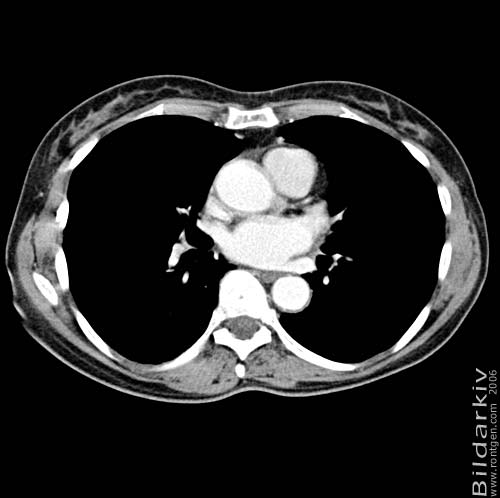

Thorax 34

Snitt över thorax med kontrast. Sk. mediastinum-fönstersättning.

CT Röntgen Helsingborgs lasarett

Mediastinum